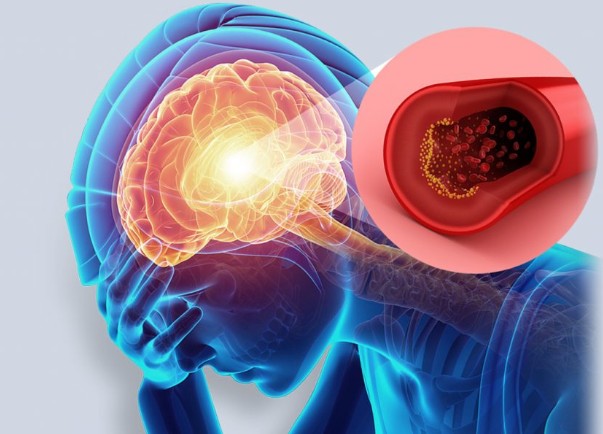

오늘은 많은 분들이 두려워하는 질환, 뇌경색의 초기 증상에 대해 이야기하려 합니다. 뇌경색은 뇌혈관이 막혀 뇌 조직이 손상되는 질환으로, 치료 시기를 놓치면 영구적인 장애를 남기거나 생명을 위협할 수 있습니다.

뇌경색 초기증상 증상이 갑작스럽게 나타나는 것이 특징이며, 응급 상황에 해당하므로 증상을 정확히 알고 신속하게 대처하는 것이 매우 중요합니다. 지금부터 뇌경색의 10가지 주요 초기 증상들을 꼼꼼히 살펴보고, 건강을 위한 첫걸음을 함께 시작해 볼까요? 🧠

뇌경색은 뇌의 어느 부위가 손상되었는지에 따라 증상이 다르게 나타납니다. 증상이 한쪽 신체에 집중되어 나타나는 것이 특징이며, 증상이 나타났다가 24시간 내에 사라지는 경우(일과성 허혈 발작)도 있지만, 이는 뇌경색의 전조 증상이므로 반드시 병원을 찾아야 합니다. 다음은 뇌경색 환자들이 흔히 겪는 10가지 주요 초기 증상입니다.